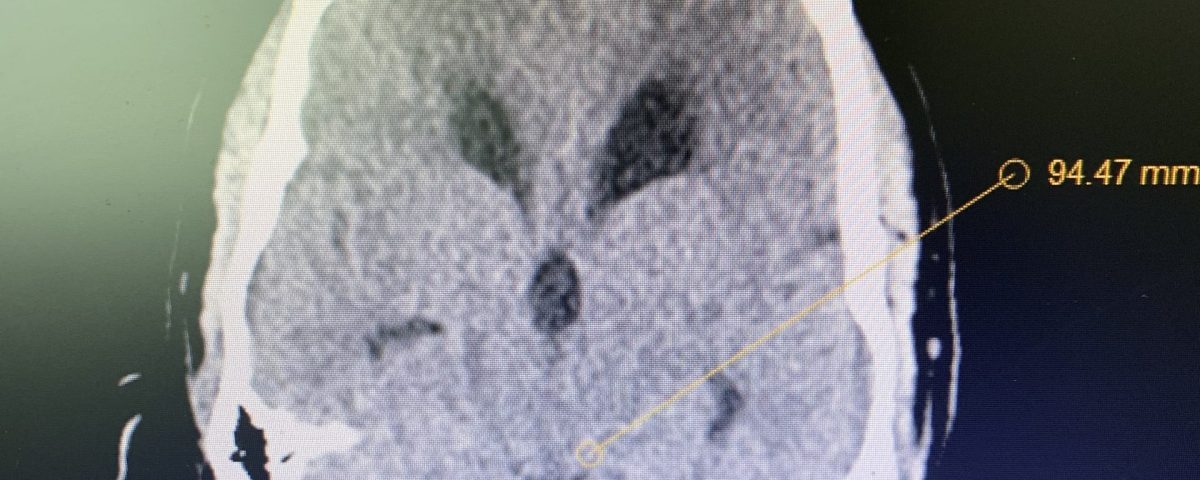

On initial examination, the patient was neurologically intact without complaints of headache. His imaging; however, did show hydrocephalus, most notably the lateral and third ventricles with a normal sized fourth ventricle. Given that the patient had no complaints, a decision was made to follow this expectantly and he was referred for a neuro-ophthalmologic evaluation, which confirmed no evidence of papilledema. MRI was otherwise negative.

Figure 1B,C: Pre-operative CT images.

Prior to shunting, a head CT was obtained and the head CT in addition to documenting a patten of obstructive hydrocephalus suggested a possible mass lesion compressing the aqueduct at its inferior aspect. Figure #1 demonstrates the hydrocephalus and the possible lesion. A decision was made at this point that the patient had obstructive hydrocephalus that was now symptomatic and he was taken for a laparoscopic-assisted ventriculoperitoneal shunt.